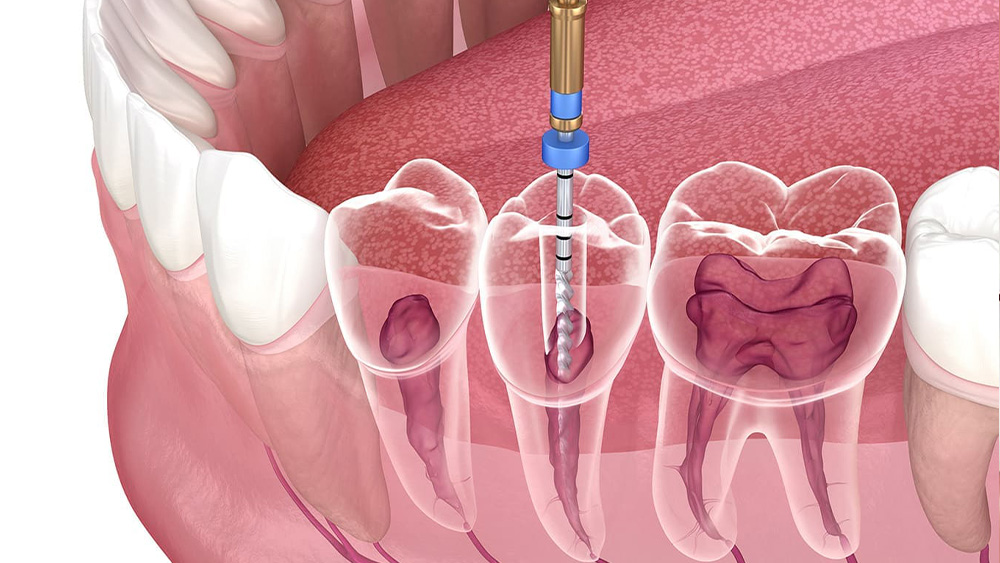

根管治療は、歯の内部にある神経や血管が通る「根管」という細い管が細菌に感染して炎症を起こしたり、壊死してしまったりした場合に行う治療です。

感染した神経や汚染物質を丁寧に取り除き、根管内をきれいに消毒し、薬剤で密閉することで、抜歯を避けてご自身の歯を残すことを目指します。

根管長測定器も併用し、歯の根の長さを正確に把握することで、適切な位置まで薬剤を届けることを大切にしています。

また、根管の清掃には、柔軟性に優れ、複雑な根管の形にもフィットしやすいニッケルチタンファイルを使用しています。

これにより、根管の壁を傷つけにくく、効率的かつ安全に感染物質を取り除くことを目指しています。

歯の内部にある神経や血管が細菌に感染し、炎症や壊死を起こしている場合に行う一般的な根管治療です。

感染した組織を丁寧に除去し、根管内を徹底的に清掃・消毒します。

その後、根管内を薬剤で緊密に充填し、細菌が再び侵入するのを防ぎます。

これにより、歯の痛みを取り除き、抜歯を避けながらご自身の歯を保存することを目指します。